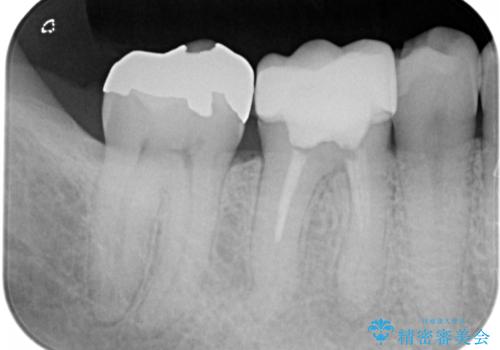

- 咬んだ時に右下奥歯に痛みがあるとの事で来院された患者様です。

歯の神経は壊死していたため、精密根管治療と補綴治療を計画しました。

セラミックでの治療を希望されたので補綴はオールセラミッククラウンでの治療を選択しました。